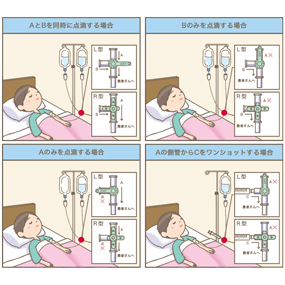

酸素投与 経鼻カニューレ・酸素マスクって流量何L 分から変更?水入れて加湿って毎回するの? 看護師。

酸素流量計の準備~カニューレの装着動画でわかる看護技術看護roo! カンゴルー。

酸素マスクによる酸素投与動画でわかる看護技術看護roo! カンゴルー。

酸素流量計の準備~カニューレの装着動画でわかる看護技術看護roo! カンゴルー。

酸素ボンベによる酸素投与動画でわかる看護技術看護roo! カンゴルー。

酸素流量計の準備~カニューレの装着動画でわかる看護技術看護roo! カンゴルー。